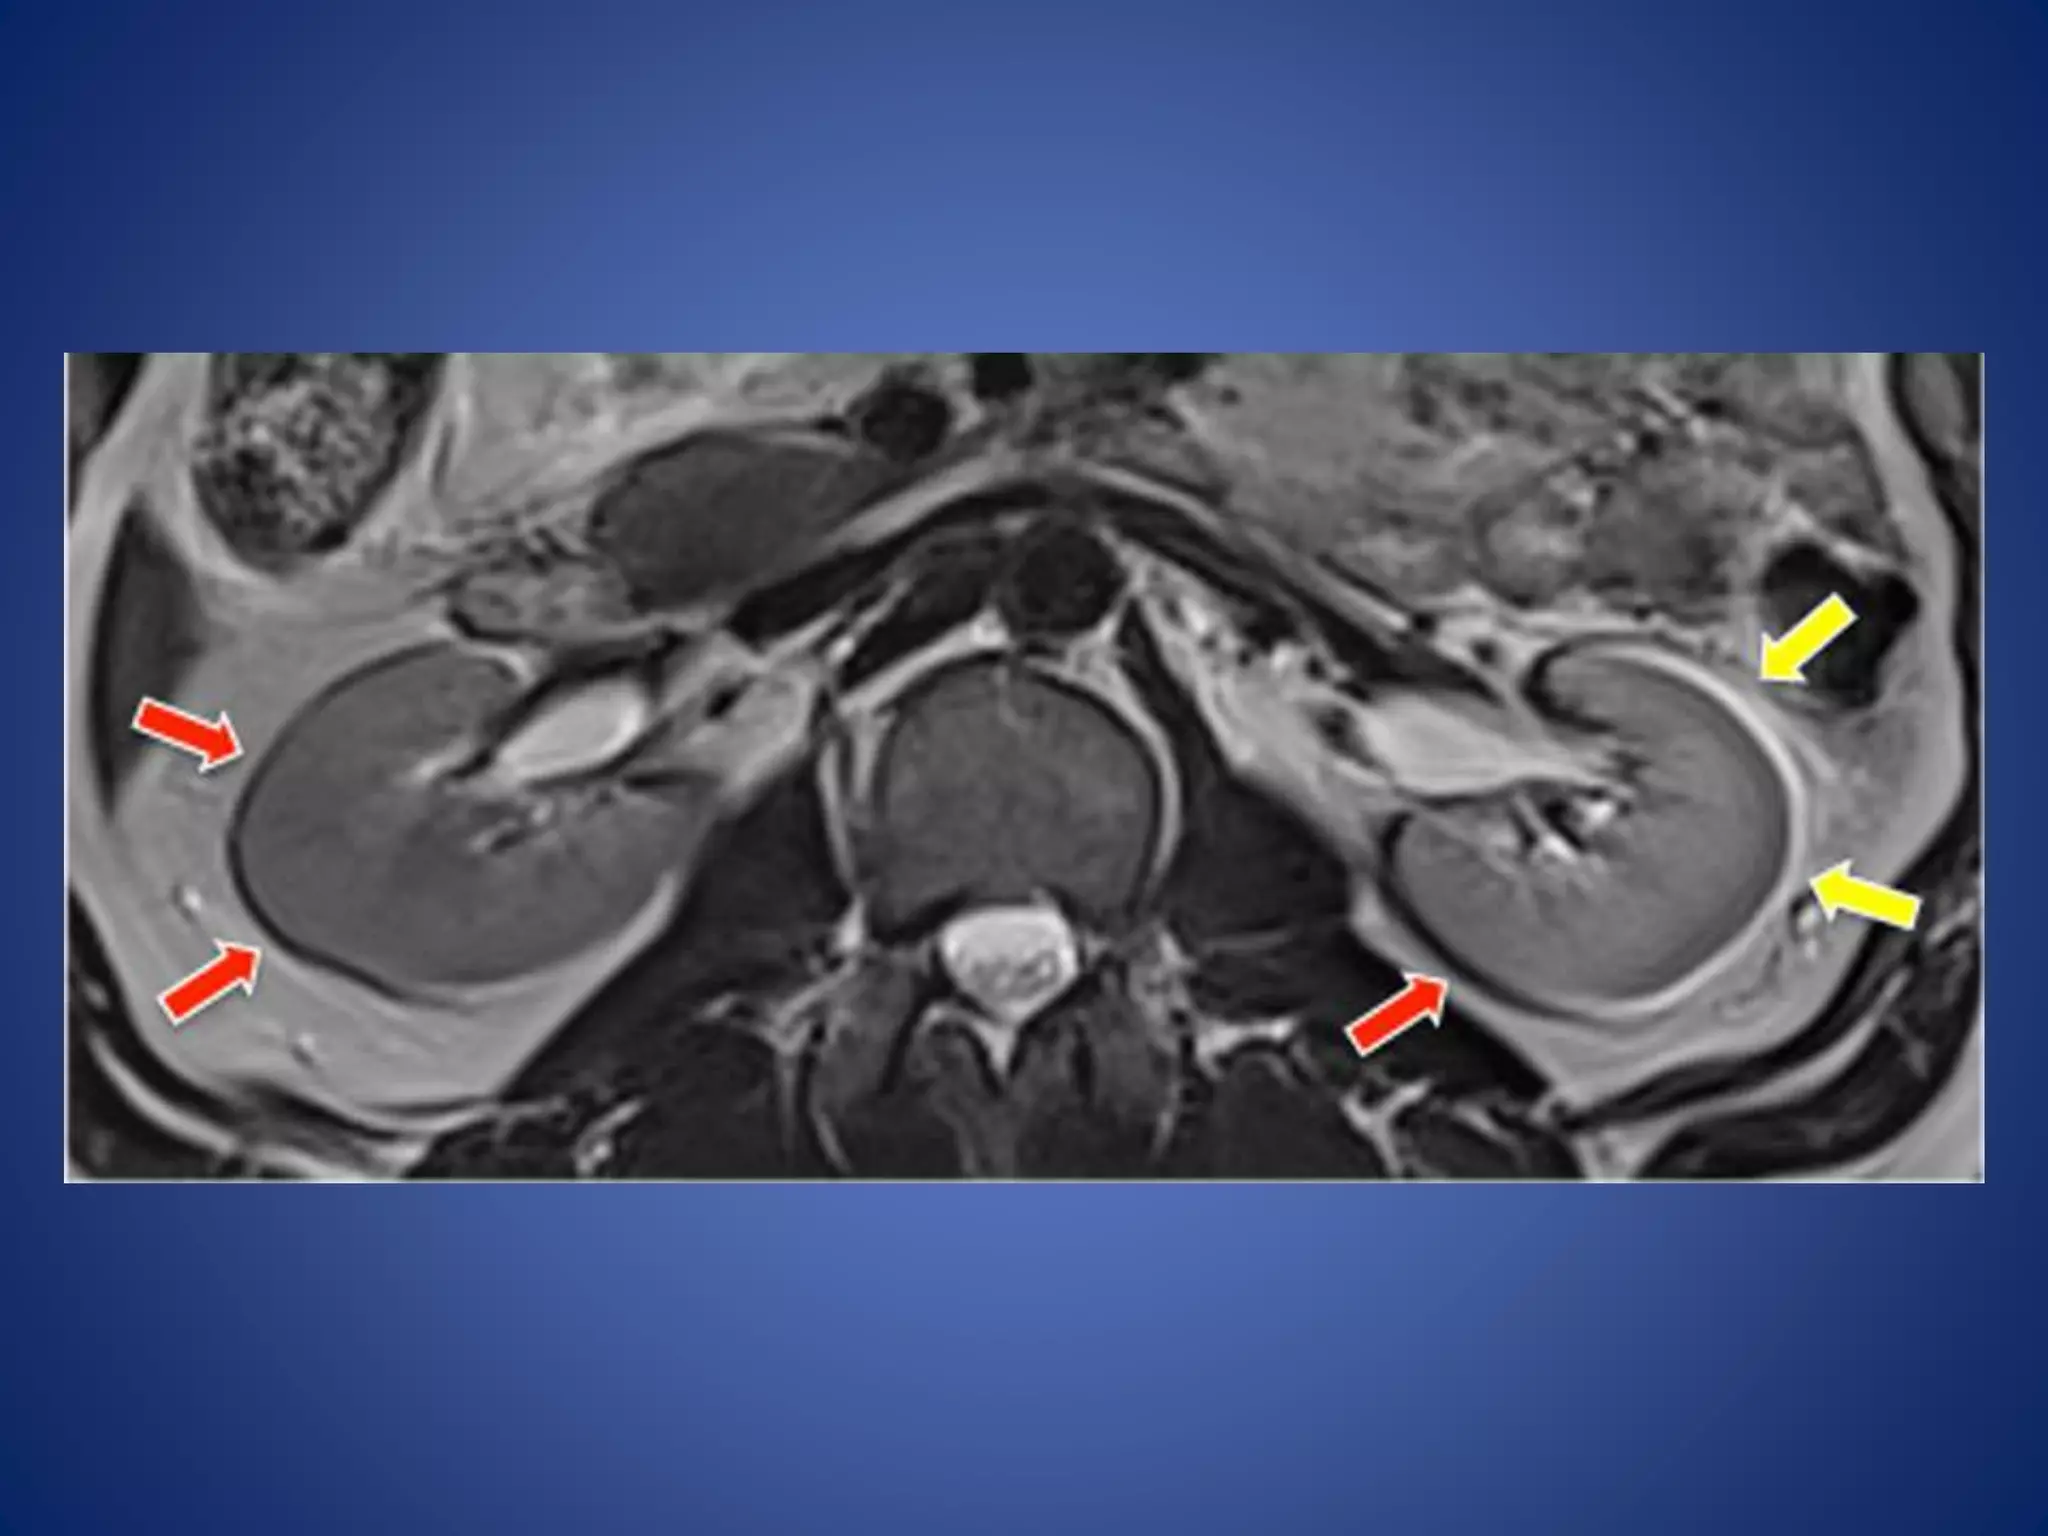

Out phase signal cancellation artifacts

• Appearance: produces a ring of dark signal

around certain organs where fat and water

interfaces occur within the same voxel.

 It degrades the image in gradient-echo pulse

sequences because gradient rephasing does not

compensate for this artifact.

• Cause:

• caused by the fact that the magnetic moments of

hydrogen precess at different frequencies, and the

differences in their phase positions are exhibited

by fat and water vectors at discrete points in time.

Out-of-phase signal cancellation show as a black line around the abdominal

organs border at the boundaries between fat and muscle

Remedy

• Selection of TE that matches the periodicity of fat and water

• Using spin echo sequences rather than gradient echo

sequences

• Using in phase TE